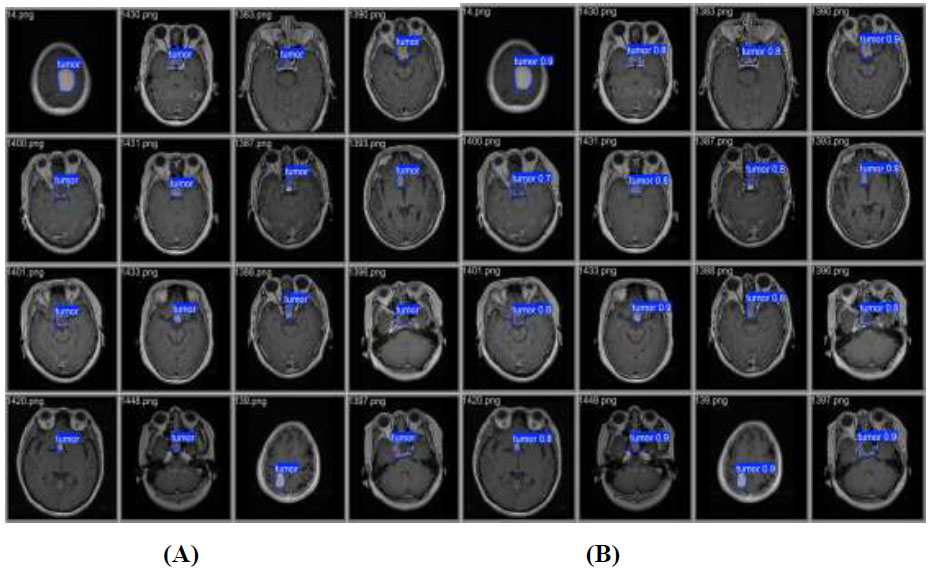

Validation and prediction batches for tumour detection (A) validation batch and (B) predication batch.

presents a visual comparison between the validation batch (Fig. 7A) and the prediction batch (Fig. 7B) generated by the YOLOv12 model. These batches are designed to improve computational efficiency and increase inference speed, facilitating the detection of tumors across various images. The validation images display tumor locations on the original images, whereas the predicted images show the model’s output after training. From this comparison, it can be concluded that YOLOv12 exhibits exceptional tumor detection performance, as evidenced by the accurate localization of tumors with bounding boxes and the corresponding confidence scores, closely aligned with the validation batch.